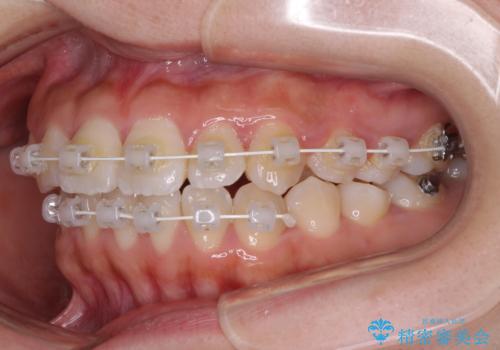

- 矯正装置

- 審美装置

- 上顎歯列と下顎前歯の叢生を気にして来院された患者様です。

上顎からワイヤー矯正を開始し、終了間際から下顎前歯の叢生解消するよう計画しました。